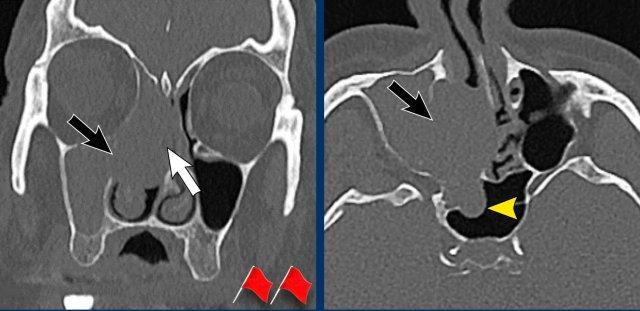

Hai dấu hiệu cảnh báo là:

- Phá hủy thành trong xoang hàm (mũi tên đen) và vách mũi (mũi tên trắng).

- Bệnh lý hoàn toàn một bên.

Ở bệnh nhân viêm mũi xoang, có thể có giãn rộng và đôi khi thậm chí phá hủy xương, nhưng bệnh lý (hầu như) luôn luôn xảy ra hai bên.

Tiếp tục với MRI…

Trên các hình ảnh STIR này, có thể thấy sự khác biệt về cường độ tín hiệu giữa xoang hàm và xoang sàng bị tắc nghẽn (mũi tên đen) và khối u (mũi tên trắng).

Ở bệnh nhân nang nhầy, toàn bộ tổn thương sẽ có cùng cường độ tín hiệu, khác với trường hợp này.